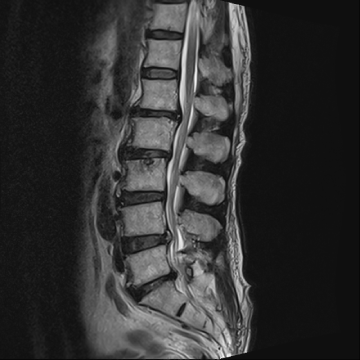

요추 협착증 수술 전·후

2020.08.30

2022.09.06

ㆍ환자 동의를 받은 자료이며, 이미지 사진은 실물과 다를 수 있습니다.

ㆍ모든 자료는 새움병원 자료입니다.